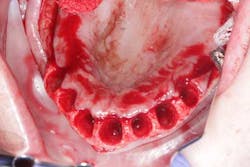

Surgery commenced. Implants on the lower arch were placed first (figures 7 and 8) and then we switched to the maxillary. The teeth were removed (figures 9 and 10) and the ridge was evened out (figures 11-13). The implants were aligned with the denture (figure 14) and then placed accordingly (figures 15-17). Healing caps were put on, and we were ready to start the restorative phase (figures 18-19).